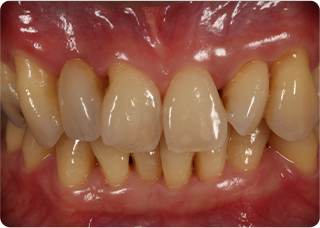

セラミッククラウン症例③

術前

術後

| 主訴 | 見た目をきれいにしたい |

|---|---|

| 治療期間/回数 | 2ヵ月、3回 |

| 価格(税込) | 110,000円(税込) |

| リスク・副作用 | セラミックの脱離・破損の可能性 |

| ポイント | 自然な色、形となるようにオーダーメイドでセラミックを盛ってクラウンを作製した。 |